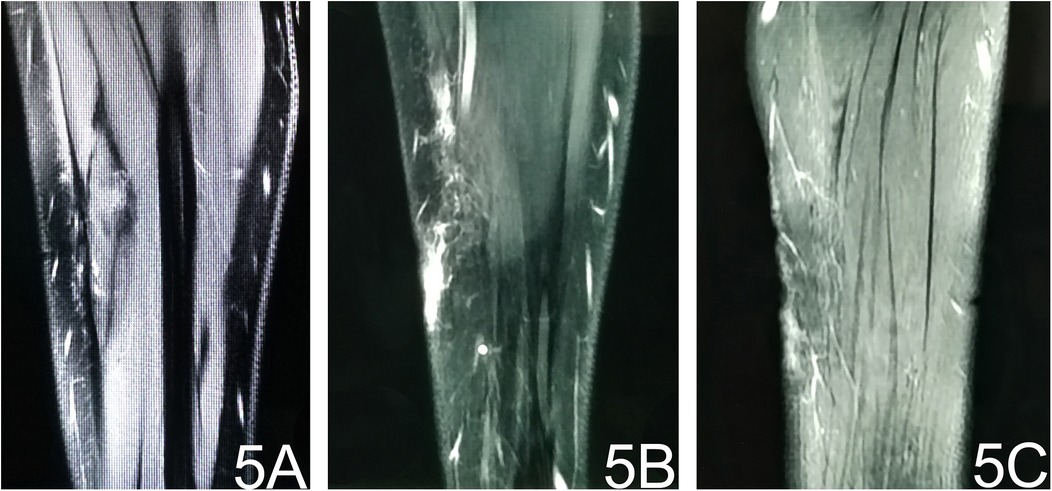

The patient was discharged on postoperative day 5 and followed up for 4 months. Repeat MRI of the left forearm showed patchy and linear long-T1/long-T2 signal areas with corresponding high signal on fat-suppressed sequences and thin, linear enhancement (Figure 5). These findings are consistent with post-operative granulation tissue and scarring; no evidence of residual or recurrent tumor was identified (Figure 5). No relevant clinical events occurred.

Figure 5. Post-operative MRI. (A) T1-weighted image reveals subcutaneous stripe- and patch-like hypointense areas at the operative site. (B) Fat-suppressed T2-weighted image shows corresponding hyperintense signal, indicating post-surgical oedema. (C) Contrast-enhanced fat-suppressed T1-weighted image demonstrates thin, patchy enhancement consistent with post-operative granulation tissue.